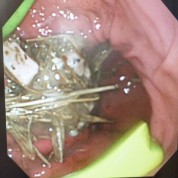

胃内異物2 串

胃内異物3 ロープのおもちゃ